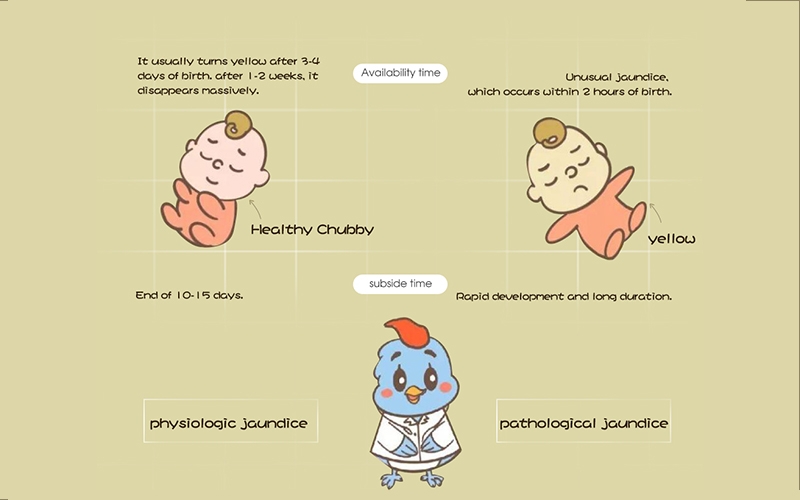

What are the causes of neonatal jaundice?

Most newborns will appear jaundice after birth, that is, the skin appears yellow obviously. This is mainly due to the disorder of bilirubin metabolism in the baby's body, which increases the bilir...